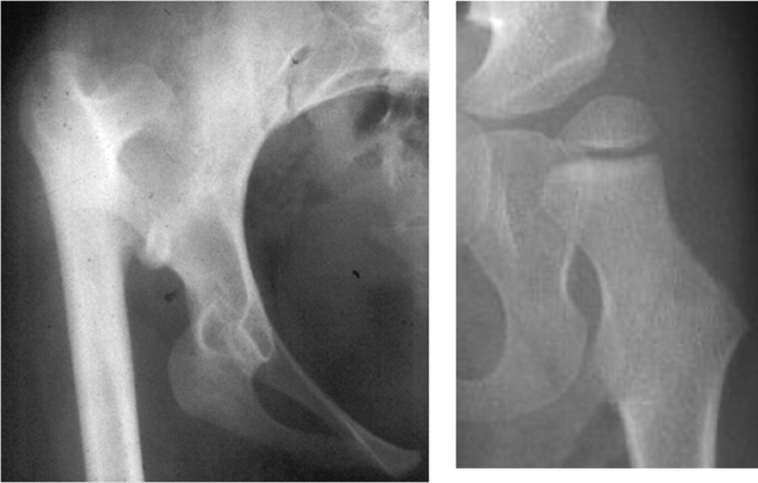

Which leg is shorter with hip dysplasia?

The left thigh is smooth but the right thigh presents with two creases. When a baby’s hip dislocation is present for several months, the hips gradually lose range of motion and the leg appears shorter because the hip has migrated upward. This baby’s right femur (thigh bone) appears to be lower(shorter) than the left.

Hip dysplasia is an abnormality in which the femur (thigh bone) does not fit together with the pelvis as it should. Symptoms are pain in the hip, limping and unequal leg lengths .